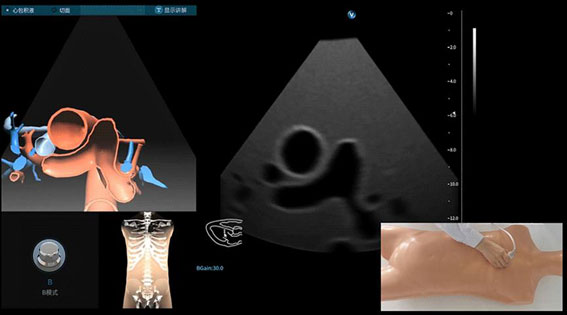

超声模拟实训系统 单机版(女)

超声模拟实训系统 单机版(女)

超声模拟实训系统 单机版(男)

超声模拟实训系统 单机版(男)

超声模拟实训系统 学生机

超声模拟实训系统 学生机

超声模拟实训系统 教师机

超声模拟实训系统 教师机